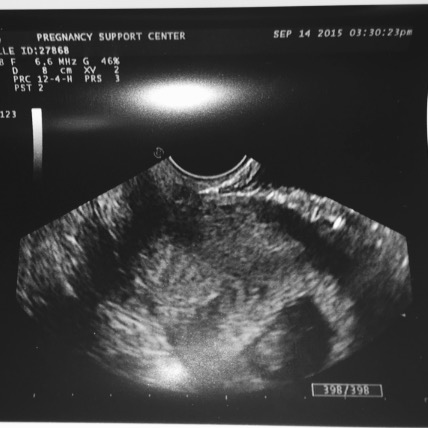

He was just our little Bebe then, but this picture brought me so much hope and happiness for the future. I showed off his first ultrasound picture to his dad so proudly. We made this beautiful little human and here this baby is. I was so happy, words cannot describe.